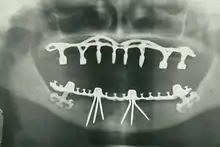

By nature of their general training, dentists, without specialization can carry out the majority of dental treatments such as restorative (fillings, crowns, bridges), prosthetic (dentures), endodontic (root canal) therapy, periodontal (gum) therapy, and extraction of teeth, as well as performing examinations, radiographs (x-rays), and diagnosis. Dentists can also prescribe medications used in the field such as antibiotics, sedatives, and any other drugs used in patient management. Depending on their licensing boards, general dentists may be required to complete additional training to perform sedation, dental implants, etc.

- Oral and maxillofacial radiology – The study and radiologic interpretation of oral and maxillofacial diseases.